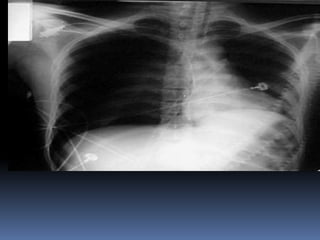

Abnormal Findings Un equalityof chest movement Hyper resonance on percussion Decrease air entry ,tachypenic Deviated trachea ,congested neck vein Tension Pneumo thorax Needle decompression & chest tube

Tension Pneumo thorax

Needle decompression & chest tube